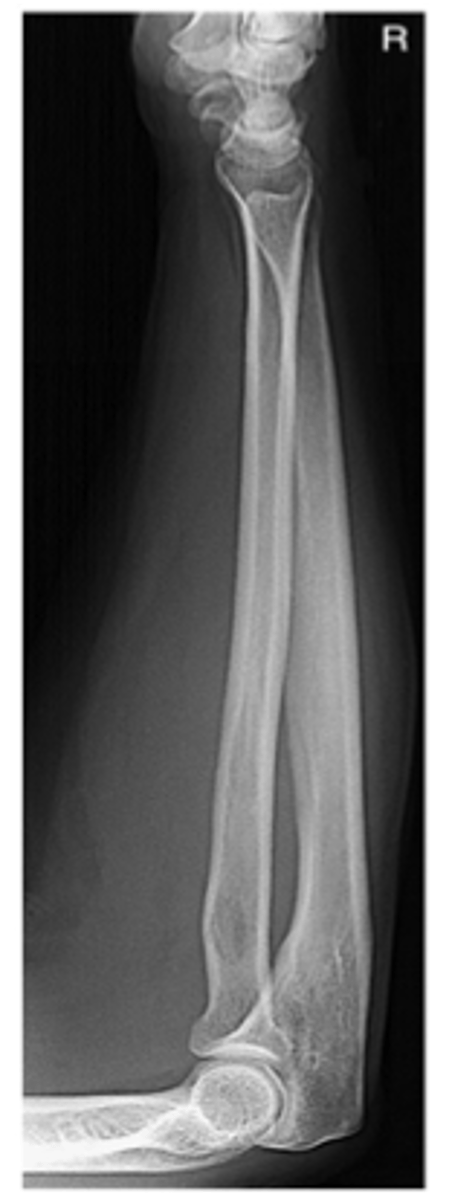

AP forearm

Lateral forearm